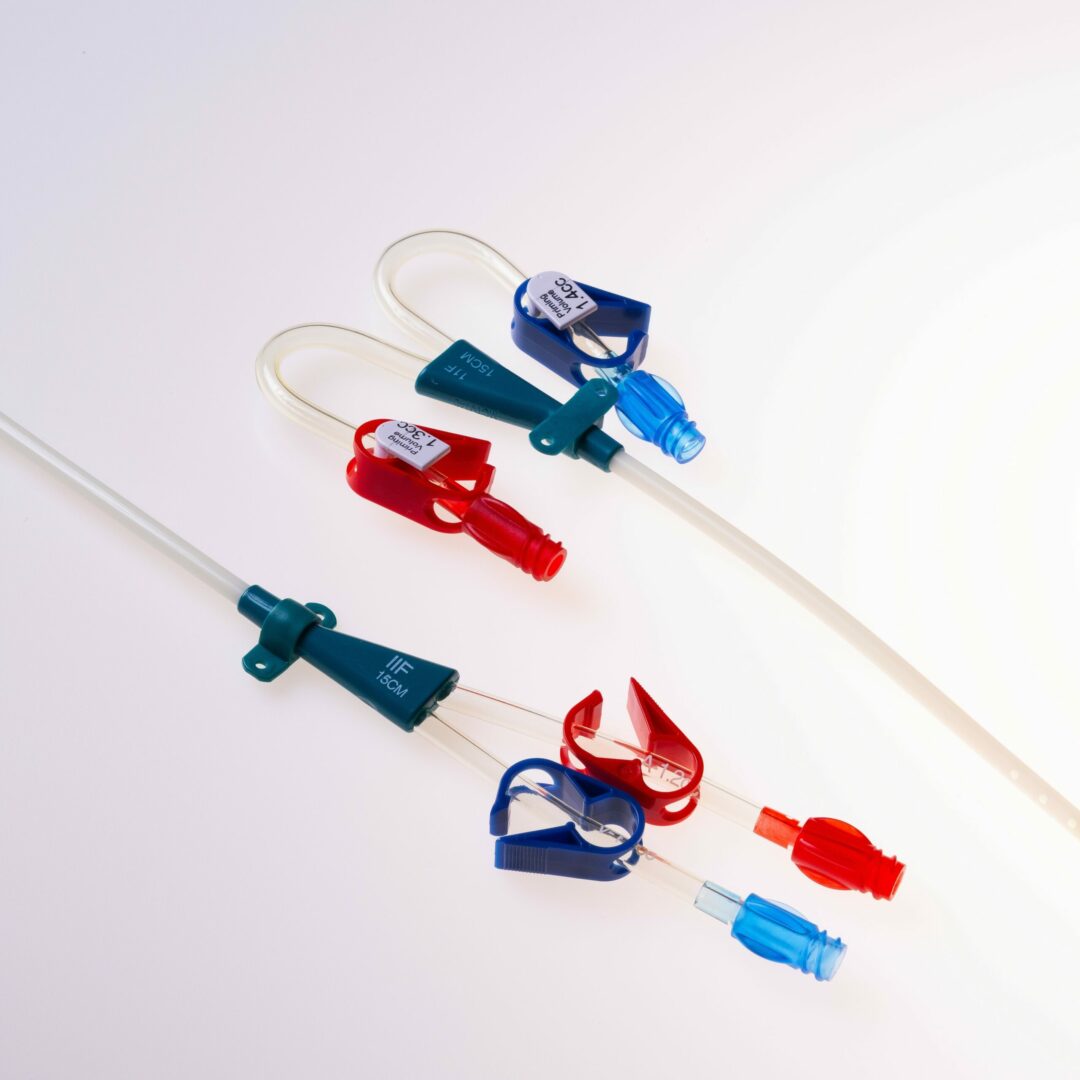

Der Duo-Flow® Side x Side ist ein Doppellumen Shaldonkatheter für die Akutdialyse, der nach der Seldinger-Technik implantiert wird.

Das Material des Dialysekatheters besteht aus Polyurethan.

Die beiden Lumina sind im Doppel – D – Design angeordnet.

Die Katheterspitze ist gestuft ( tapered ) mit einem Abstand von 3 cm zwischen dem arteriellen und venösen Schenkel.

Der Shaldonkatheter ist wahlweise mit geraden oder vorgebogenen Ansatzstücken lieferbar.

Der Duo-Flow® Side x Side ist ein Doppellumen Shaldonkatheter für die Akutdialyse.

Der Duo-Flow® Side x Side ist ein Doppellumen Shaldonkatheter für die Akutdialyse, der nach der Seldinger-Technik implantiert wird.